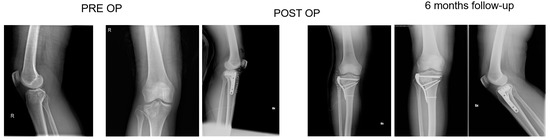

2.3. Surgical Technique and Rehabilitation

All patients had surgery within 48 hours from injury, after administration of spinal or general anaesthesia. A tourniquet was routinely positioned before starting surgical procedure; all patients were operated in a supine position, with injured leg in semi-flexion. Fractures were reduced through a percutaneous or open approach, depending on the cases; SB blocks, which size and shape were customised during surgery considering the features of bone defect for each singular patient, were positioned through a minimally invasive approach via the bony window exploited for reduction; finally, fixation of fracture line and implant were performed with screws and plates (see exemplificative Figure 1, Figure 2 and Figure 3). In one case fixation of the plateau fracture occurred through an arthroscopic approach. All the patients included in the study had identical post-operative regimen. Active knee mobilization and static quadriceps exercises were encouraged from the third day after surgery. Partial weight bearing was allowed at 4–6 weeks after surgery, and progressively increased to achieve full weight bearing at 12 weeks. Prophylaxis for thromboembolic events was obtained through administration of 4000 IU/day of low molecular weight heparin (LMWH) (enoxaparin), until full weight bearing was allowed.

Patients were clinically and radiologically assessed before surgery, at 2 weeks, and then at 1, 2, and 6 months, and 1 year after surgery. Same radiologist carried out the imaging, while evaluations were pooled by different clinicians. Clinical assessment consisted of a visual analogue scale (VAS) for the evaluation of pain, where patients were asked to report the level of pain during the day life activities; measurement of the range of motion (ROM) of the knee joint; and objective examination, intended to highlight possible alterations of surgical scar, vascular and nervous deficits, as well as infectious complications. Moreover, at 1-year follow-up Tegner Lysholm Knee Scoring Scale [21] and International Knee Document Committee 2000 (IKDC 2000) [22] questionnaires were administered during control visits, in order to evaluate patients’ subjective perception of knee function. One year after surgery, patients answered to the Short Form (36) Health Survey (SF-36) questionnaire, which scores the general physical and mental health on the basis of eight scales each ranging from 0 to 100 [23]. Radiological assessment contemplated the acquisition of anteroposterior and lateral projections radiographs at each follow-up. Images were examined in order to evaluate various features of healing process, like callus formation and maintenance of fracture reduction; as well as to detect the presence of possible malalignment, pseudo-arthrosis, bone non-unions, and articular surface depression or widening (see exemplificative Figure 1, Figure 2 and Figure 3).

At six months, X-rays images showed that all 34 fractures displayed a good consolidation rate, as confirmed by radiological reports. In particular, radiolucency of the xenografts was assessed [20], which became progressively more similar to that of the surrounding healthy bone tissue (see exemplificative Figure 1, Figure 2 and Figure 3 and comparative images in Figure 4).

Comparison with the current literature is challenging, due to the lack of standardised follow-up protocols and differences in quantitative assessment of outcomes among the studies. However, the implant of SB in our series resulted in a standard return to knee mobilisation, as highlighted by the mean ROM at last follow-up and the return to partial weight bearing at 4–6 weeks. We also described no complications, like infections and joint subsidence, if compared to similar studies present in the medical literature [31]. Radiological follow-up did not show diastasis or depressions of tibial articular surface excluding the incomplete subchondral reductions documented at the first post op X-ray, which means that mechanical properties of SB were adequate for high and complex forces which the plateau commonly undergoes. At each follow-up, the radiolucency of implants was progressively more similar to radiolucency of the surrounding bone (see exemplificative Figure 1 and Figure 2). We interpreted this evidence as supporting the thesis that SB would have been able to integrate with autologous bone tissue, favouring deposition of new bone matrix within an ongoing remodelling process: indeed, there is a clear morphological pattern on the evolution of the standard X-Ray imaging series over time which shows the substitution of the grafted material with a more homogeneous signal in the area of graft implant. As already demonstrated, the progressive remodelling together with an increase of the mineral signal cannot be dependent on the active remodelling of the graft per se given it is a decellularized matrix. Therefore, the increase in the density over time depends on novel mineral matrix apposition likely induced by the graft, as previously shown both in vivo and in vitro [7,20].

Figure 1. Fifty-seven-year-old patient, X-rays: preoperative, postoperative and control at 6 months follow up of a Shatzker type 2 fracture, AO 41 B1.3.